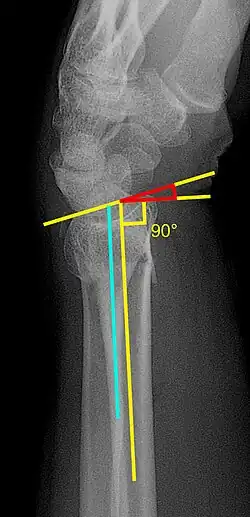

- Volar or dorsal tilt - A line is drawn joining the most distal ends of the volar and dorsal side of the radius. Another line perpendicular to the longitudinal axis of the radius is drawn. The angle between the two lines is the angle of volar or dorsal tilt of the wrist. Measurement of volar or dorsal tilt should be made in true lateral view of the wrist because pronation of the forearm reduces the volar tilt and supination increases it. When dorsal tilt is more than 11 degrees, it is associated with loss of grip strength and loss of wrist flexion.[5]

- Radial inclination - It is the angle between a line drawn from the radial styloid to the medial end of the articular surface of the radius and a line drawn perpendicular to the long axis of the radius. Loss of radial inclination is associated with loss of grip strength.[5]

- Radial length - It is the vertical distance in millimetres between a line tangential to the articular surface of the ulna and a tangential line drawn at the most distal point of radius (radial styloid). Shortening of radial length more than 4mm is associated with wrist pain.[5]

- Ulnar variance - It is the vertical distance between a horizontal line parallel to the articular surface of the radius and another horizontal line drawn parallel to the articular surface of the ulnar head. Positive ulnar variance (ulna appears longer than radius) disturbs the integrity of triangular fibrocartilage complex and is associated with loss of grip strength and wrist pain.[5]